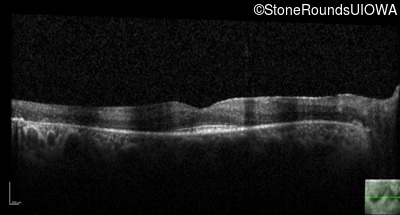

Optical Coherence Tomography - Left - 20/30

Exemplar / OCT Stack

OCT Stack